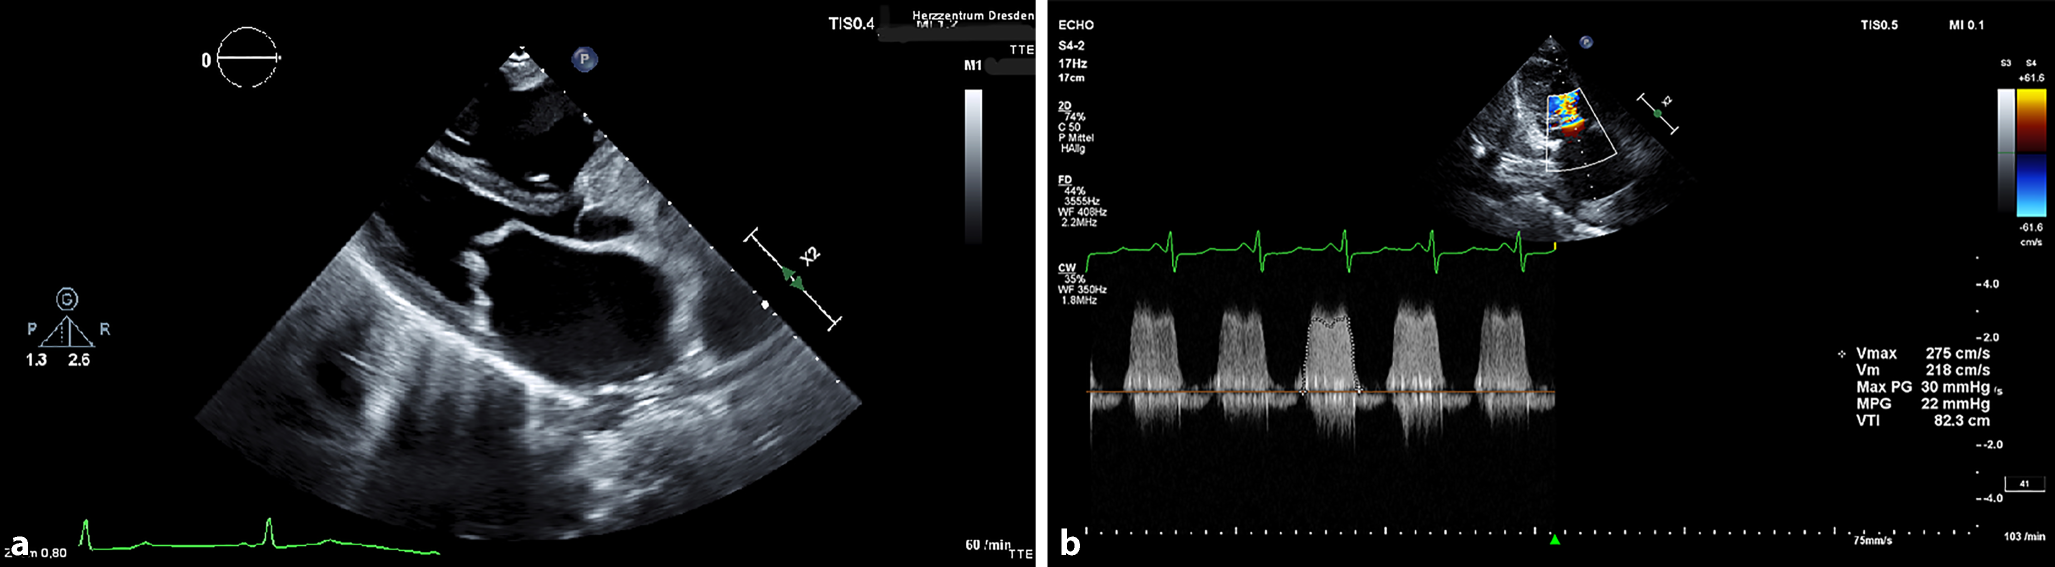

The computed tomography (CT) revealed a pulmonary embolism (PE) as well as a pleural effusion. Transthoracic echocardiography showed evidence of a severe mitral stenosis, with a mean pressure gradient of 22 mm Hg and an orifice area of 0.6 cm2. The findings are presented in Fig. 1.

a Parasternal long-axis view of the mitral valve stenosis with transthoracic echocardiography. b Pressure measurement of the mitral valve stenosis with continuous wave (CW) doppler with transthoracic echocardiography